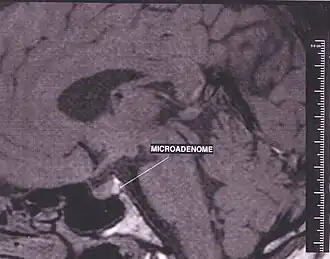

Adénomes

L'hypersécrétion est due le plus souvent à un adénome. Les adénomes sont par ordre de fréquence :

- adénome lactotrope (sécrétion de prolactine d'où hyperprolactinémie) ;

- adénome somatotrope (sécrétion de GH d'où acromégalie) ;

- adénome gonadotrope ou non-sécrétant (synthèse de LH et FSH, pas toujours libérée dans le sang) ;

- adénome corticotrope (sécrétion d'ACTH d'où maladie de Cushing) ;

- adénome thyréotrope (très rare, hyperthyroïdie par excès de TSH) ;

- il existe des adénomes mixtes : somatotrope et lactotrope surtout, mais d'autres associations sont possibles.

On parle de « micro adénome » (moins de 1 cm) ou de « macro adénome » hypophysaire (plus de 1 cm).

Un macro adénome peut fournir un excès d'hormone(s) et, dans le même temps, comprimer l'hypophyse saine, entraînant un déficit d'une ou plusieurs autres hormones.